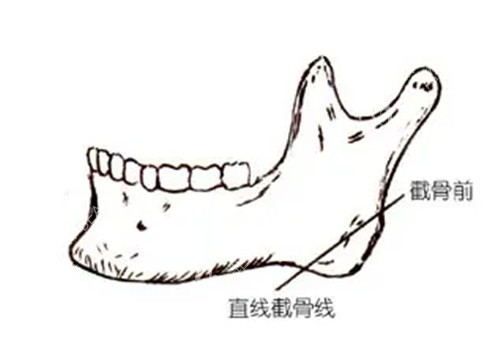

什么是智能化更准截骨

李运峰较早引入3D技术辅助手术。术前用CT数据重建三维骨骼模型。可在术前模拟术后结果并进行方案设计。术中采用导航系统实时追踪截骨位置。将截骨误差控制在极低范围内。

这项技术的实际好处

更准截骨能大幅降低手术风险。尤其能减少对面部神经的损伤。术后肿胀程度减轻且改善更快。有患者反馈一周左右可改善正常生活。